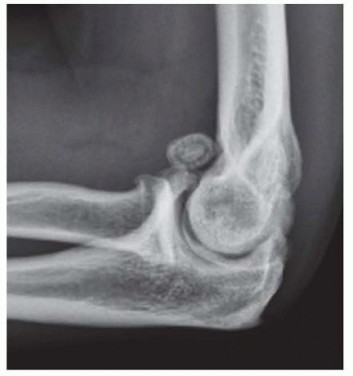

Surgical Management of Traumatic Conditions of the Elbow: Interposition Arthroplasty